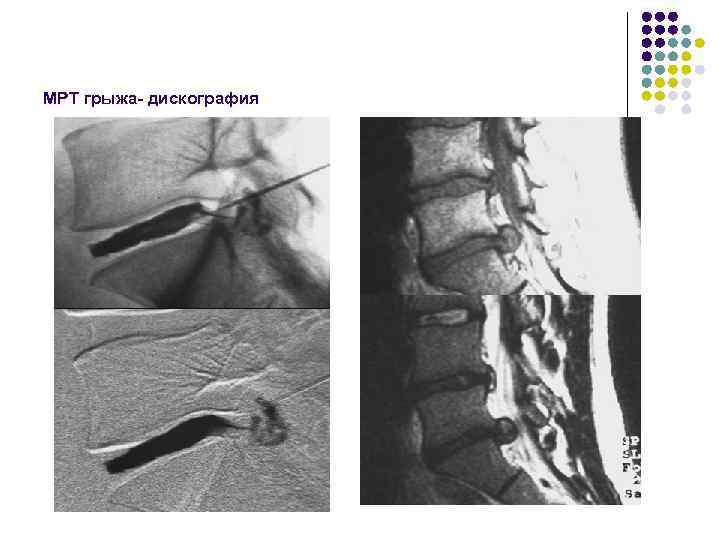

Классификация выпячивания дистрофически измененного диска за пределы позвонка (МРТ) По данным института нейрохирургии им. Н. Н. Бурденко • выбухание • протрузия • выпадение (грыжа) • грыжа с секвестрацией По данным медицинского центра банка РФ • протрузия диска (смещенное ядро растягивает фиброзное кольцо, но не перфори-рует его) • пролапс диска (части диска перфорируют фиброзное кольцо и выходят в эпидуральное пространство) • секвестр диска (вещ-во пульпозного ядра мигрирует выше или ниже уровня диска)

МРТ грыжа- дискография